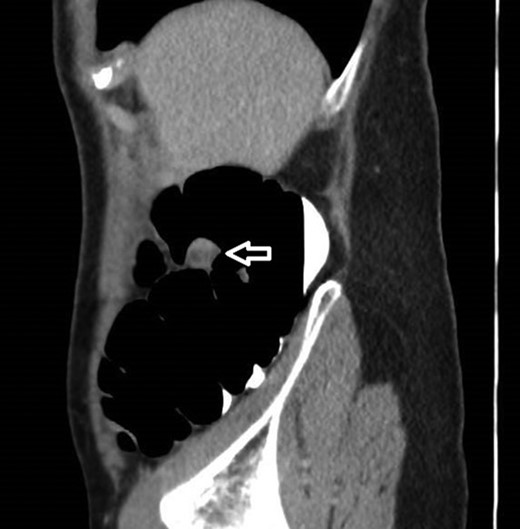

12 mm polypoidal mass (white arrow) visible on sagittal image of post-contrast CTVC.

In view of this CT Colonoscopy was performed, alongside a CT Chest examination. This showed a 12 mm lesion arising from the lateral wall of the ascending colon. It appeared rounded and mural-based, and displayed irregular peripheral enhancement post-contrast. It did not conform with a lipomatous lesion, with an average internal density of approximately 40 HU. No other colonic lesions were demonstrated, and no locoregional adenopathy or distant metastases were identified.